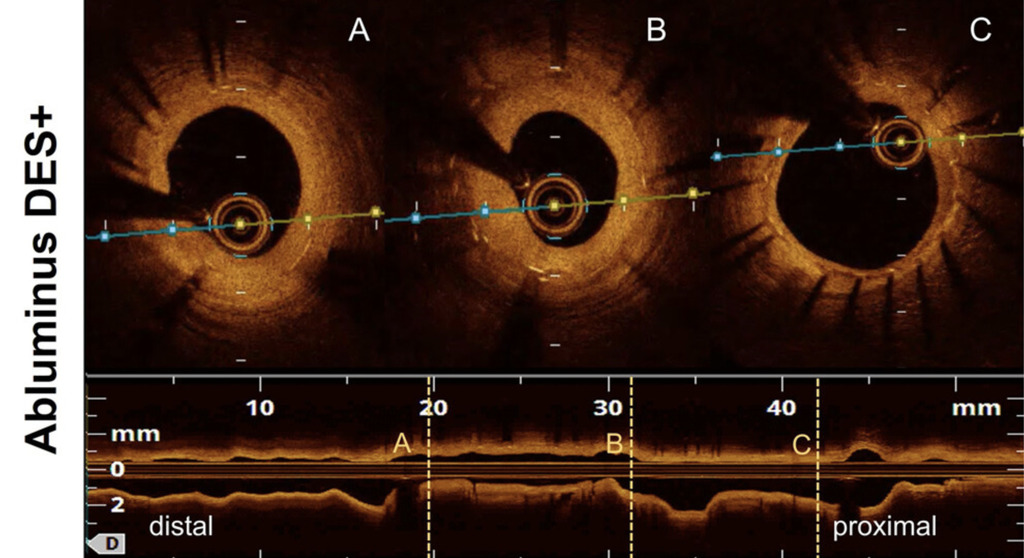

FDA Clears Optical Coherence Tomography System for AI-Enabled High-Resolution Imaging of Coronary Plaque  www.diagnosticimaging.com May 8, 2026, 2:35 p.m.

Facilitating enhanced real-time visualization for percutaneous coronary intervention (PCI) procedures, the Ultreon 3.0 optical coherence tomography platform reportedly combines high-resolution imaging with AI-powered insights on stent sizing and positioning.